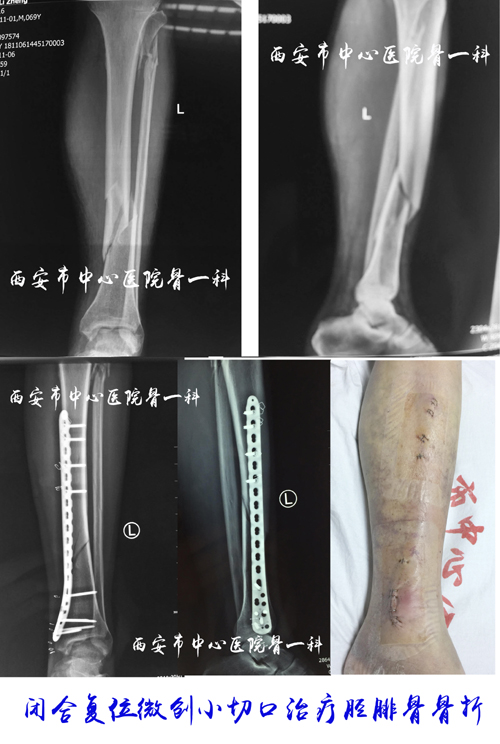

微创病例图片

闭合复位经皮螺钉内固定治疗胫腓骨悬崖撒手